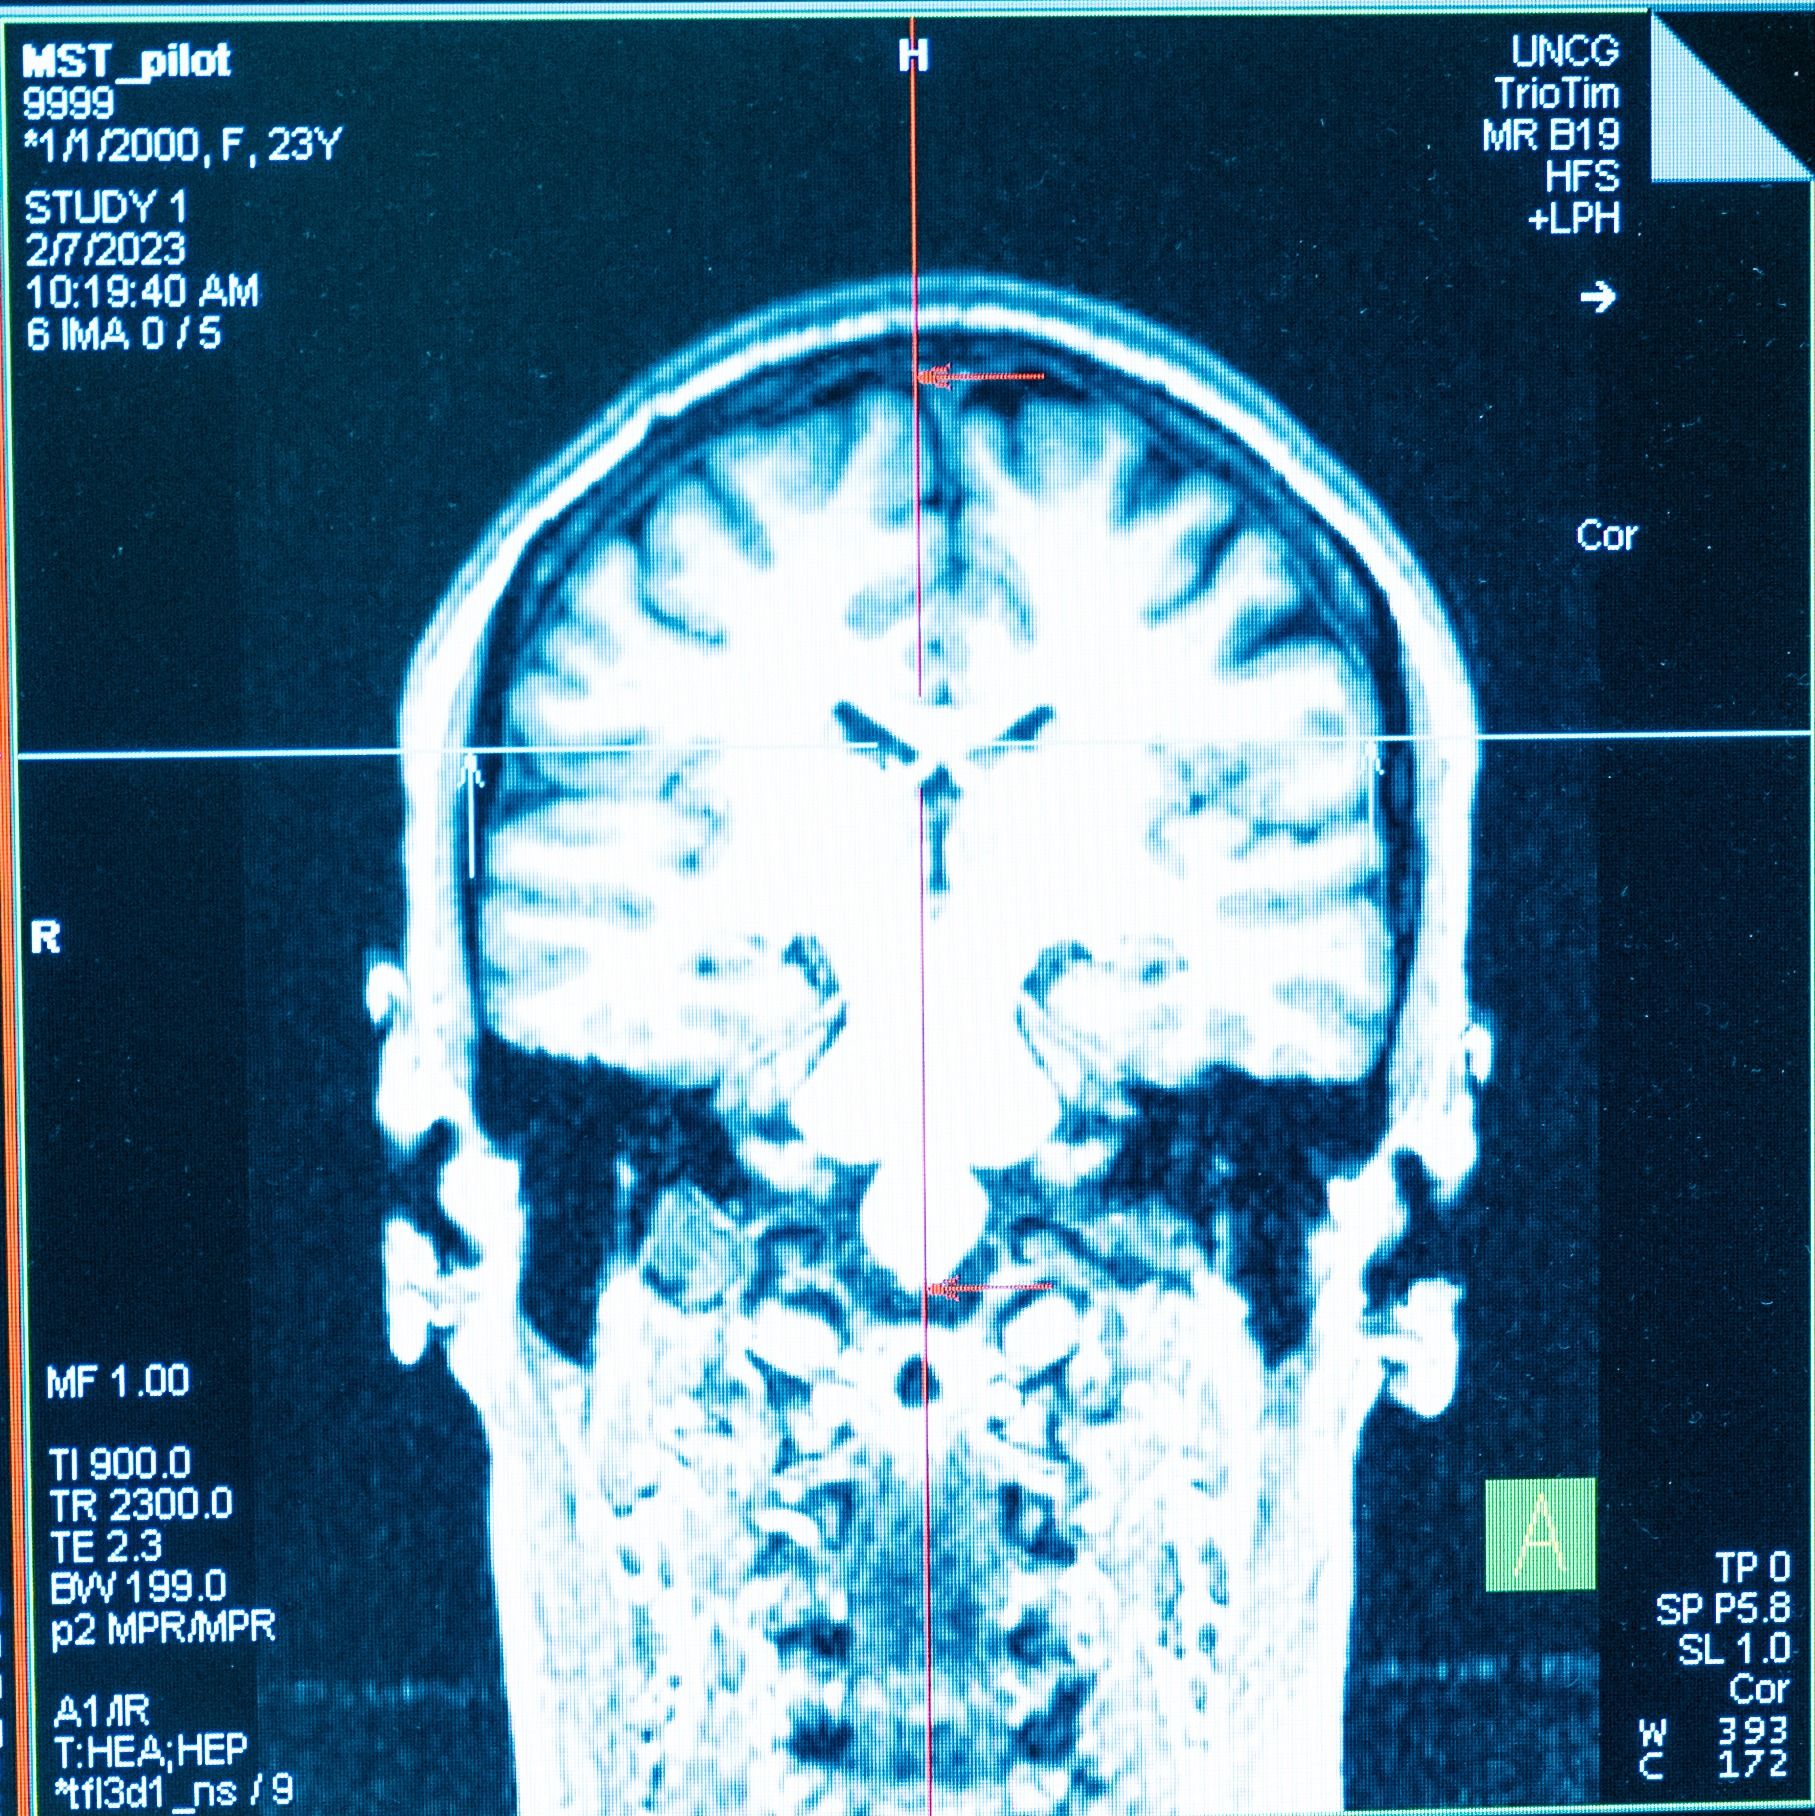

UNCG researchers are using a magnetic resonance imaging machine, or MRI, to peer inside joints and take pictures of study volunteers’ brains. Their goal is to better understand how our bodies and brains function – and why things go wrong – to find ways to prevent common problems.

MRIs create high-resolution images of tissues that have water in them – virtually all tissues in the human body.

Powerful magnets in the machine cause protons in water molecules to align, and then the machine emits radio waves that tickle those water molecules. The water molecules give off energy the machine detects to create pictures of tissues. It can even measure blood flow in the brain.